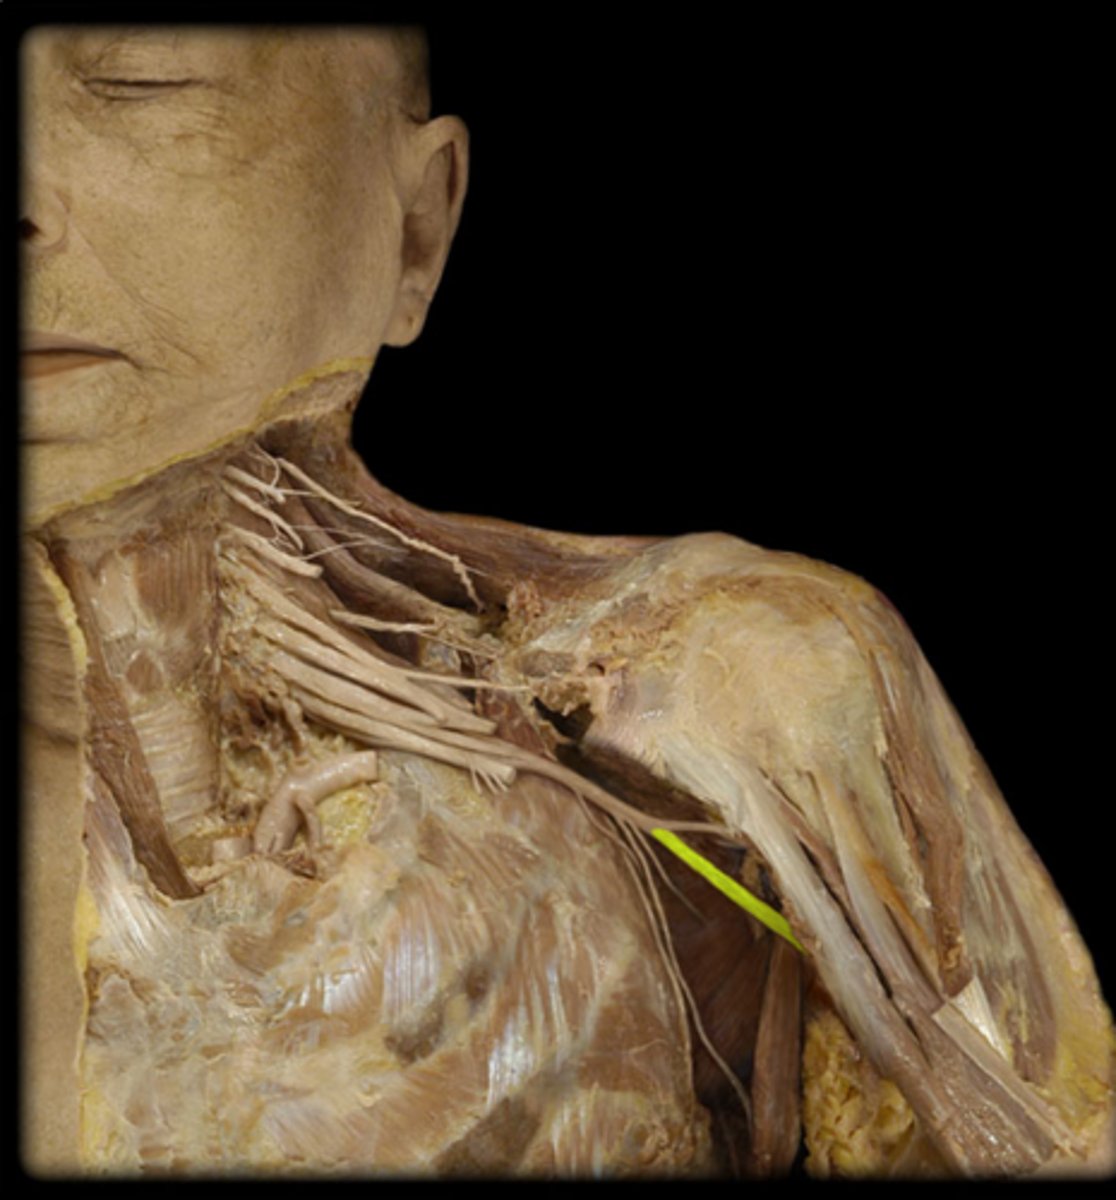

Musculocutaneous n.

coracobrachialis, biceps brachii, and brachialis muscles

Median n.

Name this structure.

Ulnar n.

medial aspect (pinky side) of the forearm